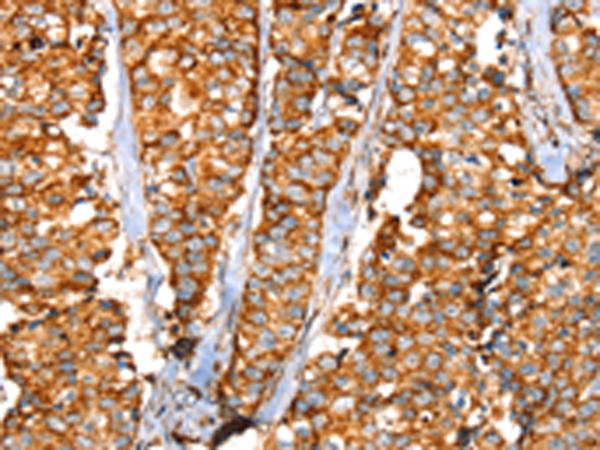

分类: 科研抗体货号: P05340别名: MSK; SIK; SNF1LK应用: IHC反应种属: Human, Mouse, Rat